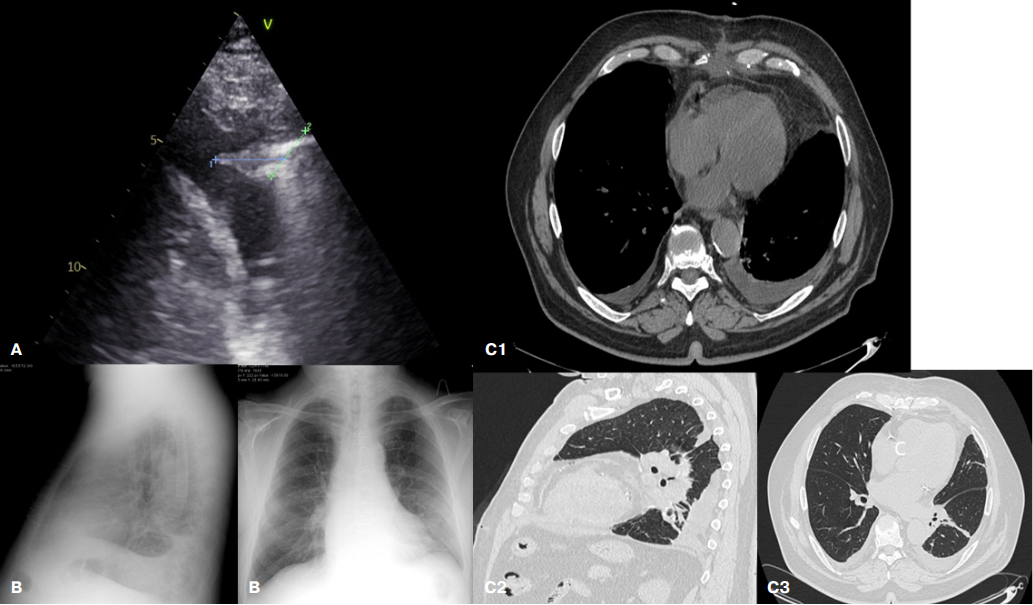

На 4 сут. после операции легочных симптомов нет, появление лихорадки до 38,5 C, сатурация крови 96%. В крови лейкоцитоз 17×109/л со сдвигом формулы до юных форм (миелоциты 2%, метамиелоциты 6%, нормобласты 1%), повышение СОЭ до 62 мм/ч и СРБ до 250 мг/л. Выполнено УЗИ лёгких (рис. 2 А). По лопаточной линии в 7 межреберье с обеих сторон в проекции нижних долей доли лёгких выявлены участки консолидации размерами справа 16×16 мм, слева 24×19 мм неоднородной эхогенности без васкуляризации, подвижность легких снижена. Около зон консолидации с обеих сторон — множественные (от 3 до 7 в поле зрения) тонкие В-линии. Над передними отделами легких — А-профиль. В плевральных полостях жидкость справа 100 мл, слева 220 мл. Заключение: участки субплевральной консолидации без васкуляризации малых размеров в проекции нижних долей лёгких, двусторонний легочный интерстициальный синдром, гидроторакс. С учетом малого размера зоны консолидации и отсутствия ее васкуляризации картина больше соответствует ателектазам, а не инфильтрации.

Выполнена рентгенография ОГК в прямой и левой боковой проекциях (рис. 2 В). В левой плевральной полости определяется жидкость, частично осумкованная, левый купол диафрагмы в заднем отделе на фоне коллабированной легочной ткани не виден, в прикорневой зоне S10 левого легкого вероятна перибронхиальная инфильтрация.

Для уточнения диагноза НП проведена КТ ОГК (рис. 2 С). Обнаружена тяжистость подкожно-жировой клетчатки в области послеоперационного шва, единичные пузырьки газа. Средостение не смещено. Сердце не увеличено. Небольшое количество жидкости в полости перикарда вдоль правой латеральной поверхности сердца, толщиной до 6 мм. В плевральных полостях вдоль по задней поверхности лёгких — свободная жидкость, плотностью -8..+12HU (соответствует транссудату), объемом справа до 250 мл, слева до 350 мл. Задние и наддиафрагмальные отделы S9, S10 с обеих сторон минимально коллабированы жидкостью. Достоверно очаговых изменений, консолидации по типу бронхо-/плевропневмонии, а также по интерстициальному типу, характерному для вирусной пневмонии, не выявлено. Тяж по типу субсегментарного ателектаза в S8 слева. Архитектоника паренхимы сохранена. Заключение: двусторонний гидроторакс, более выраженный слева с коллабированием прилежащих сегментов. Достоверных КТ-признаков пневмонии не выявлено. Ранние КТ-признаки формирования воспалительного инфильтрата малых размеров на уровне электродов временного электрокардиостимулятора.

Рис. 2. Лучевые методы исследования легких пациента П.

Примечание: А — УЗИ (правая задняя нижняя зона, В-режим), В — рентгенография, С — спиральная КТ ОГК (С1 — аксиальная проекция в средостенном окне на уровне мечевидного отростка грудины, С2 — сагиттальная проекция в легочном окне на уровне базальных сегментов левого лёгкого, С3 — аксиальная проекция в легочном окне на уровне левого предсердия).